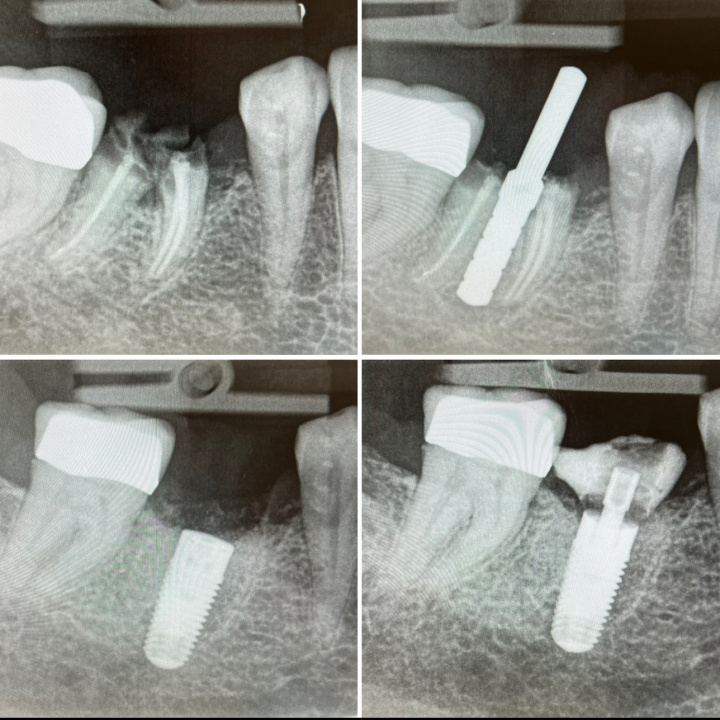

Elles visent à reconstruire les volumes osseux ou gingivaux perdus après une extraction ou une longue édentation. Parmi les techniques les plus courantes figurent la greffe osseuse, le sinus lift (élévation sinusienne), et les régénérations osseuses guidées.

Ces interventions créent un environnement stable et suffisant pour accueillir un implant. Elles peuvent nécessiter plusieurs mois de cicatrisation avant la pose de l’implant. La qualité de l’os est essentielle pour assurer la stabilité et la durabilité de l’implant.

Ces chirurgies sont planifiées avec précision à l’aide d’imagerie 3D. Elles sont réalisées sous anesthésie locale ou sédation. Bien encadrées, elles permettent d’élargir les indications de l’implantologie.